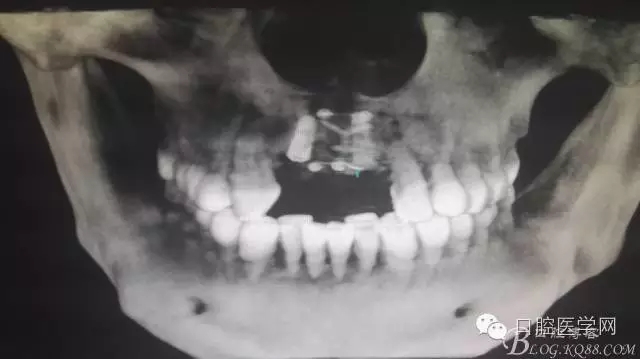

植入種植體左側(cè)3510,右側(cè)4010,植骨Bioss,蓋膜Cytoplast。骨膜減張垂直褥式縫合加間斷縫合。

之所以選擇Bioss是考慮其降解速度較慢,種植體接觸大面積為自體骨,Bioss可以很穩(wěn)定的緩慢吸收逐步引導(dǎo)骨再生。

后期的修復(fù)工作由之前的轉(zhuǎn)診醫(yī)生后續(xù)處理,由于GBR過程骨膜減張導(dǎo)致角化牙齦不足3mm,建議角化牙齦移植改變其更好的牙齦生物型。